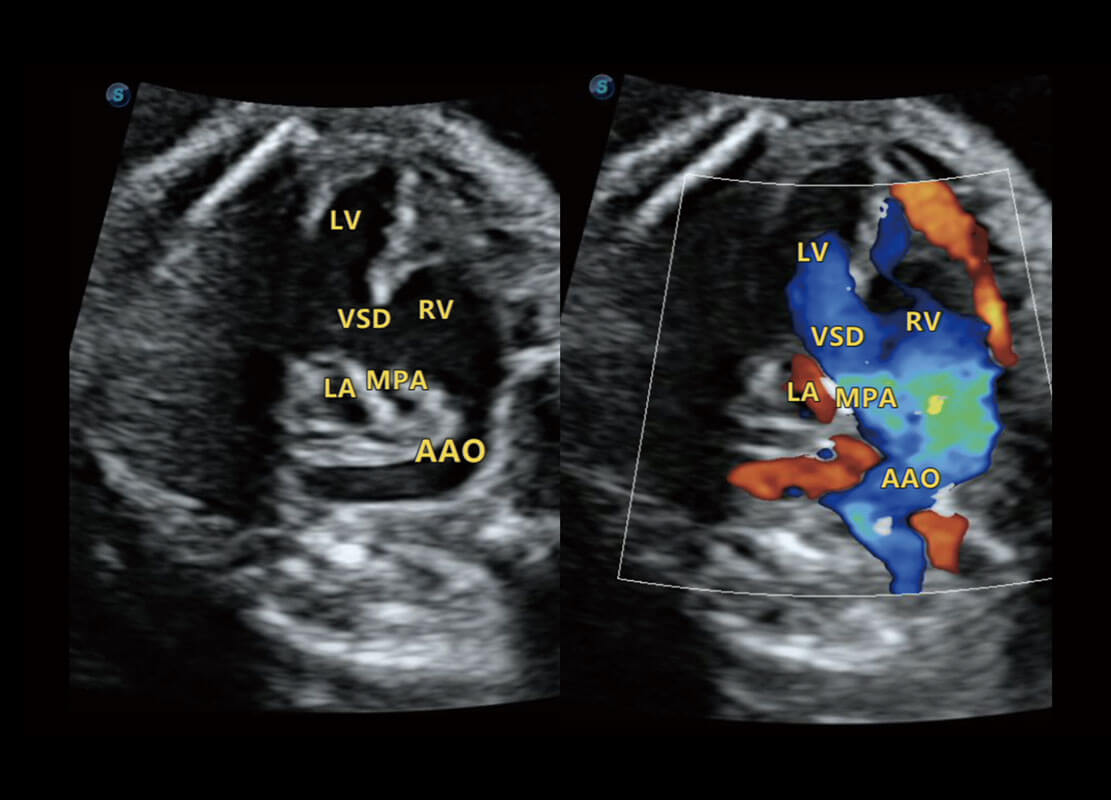

P60搭载一系列胎儿心脏成像技术,实现精细的胎儿心脏评估。

右室双出口